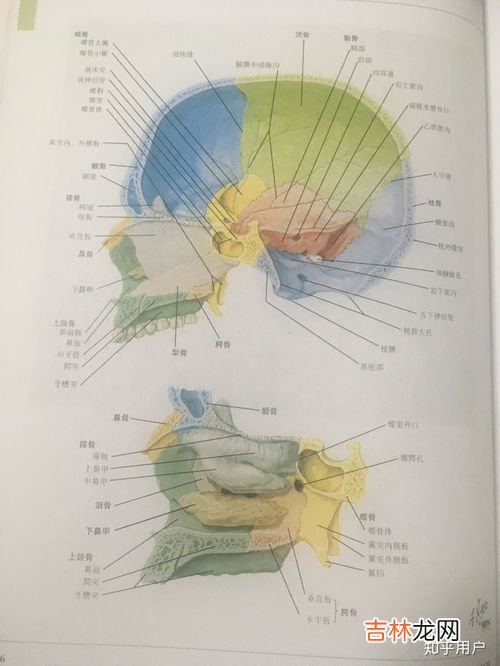

1、筛骨在哪里筛骨 [shāi gǔ] 位于蝶骨的前方和两眶之间,上接额骨鼻部并突入鼻腔内 。筛骨前面观呈中字形 。全骨分为篩板、垂直板和篩骨迷路三部分 。水平位的中间骨板为篩板,在水平方向上分隔颅腔前部与鼻腔,板的正中有向上突起的鸡冠,其两侧有许多筛孔 。篩板正中向下延伸的正中矢状位骨板为垂直板 , 参与构成骨性鼻中隔 。篩骨迷路位于垂直板两侧,由菲薄的骨片围成许多含气小腔为筛小房,又称筛窦 。迷路内侧壁上的上、下两个弯曲的骨片,分别为上鼻甲和中鼻甲 。

筛骨,解剖学同名骨 。筛骨分为三部分:

篩板

是多孔的水平骨板,构成鼻腔的顶,板的前份有向上伸出的骨脊称鸡冠 。

垂直板

自篩板中线下垂,居正中矢状位 , 构成骨性鼻中隔上部 。

篩骨迷路

位于垂直板两侧 , 由菲薄骨片围成许多小腔,称筛窦 。迷路内侧壁具有两个卷曲的小骨片,即上鼻甲和中鼻甲 。迷路外侧壁骨质极?。钩煽舻哪诓啾冢?称眶板 。

筛骨是位于蝶骨的前方和两眶之间,上接额骨鼻部并突入鼻腔内 。筛骨前面观呈中字形 。全骨分为篩板、垂直板和篩骨迷路三部分 。水平位的中间骨板为篩板 , 在水平方向上分隔颅腔前部与鼻腔,板的正中有向上突起的鸡冠,其两侧有许多筛孔 。篩板正中向下延伸的正中矢状位骨板为垂直板,参与构成骨性鼻中隔 。篩骨迷路位于垂直板两侧 , 由菲薄的骨片围成许多含气小腔为筛小房,又称筛窦 。迷路内侧壁上的上、下两个弯曲的骨片 , 分别为上鼻甲和中鼻甲 。